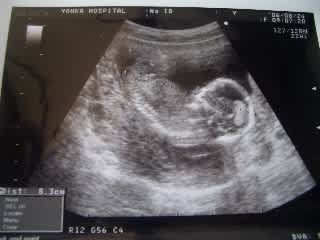

妊娠15週目 15w0d 6d のエコー写真とエピソード 妊娠4ヶ月 Cozre コズレ 子育てマガジン